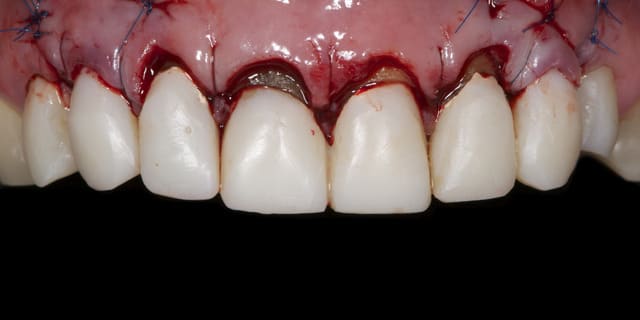

Évidemment tu as parfaitement raison c'est pourquoi lors de la confection des prov sur 13-23 je n'ai pas touché la racine pour adapter les prov. Ainsi lors de la chir , j'ai effectué une plastie vestibulaire radiculaire qui a permis de déplacer coronairement la limite prothetique de 2 mm env..

Ainsi j'ai pu effectué classiquement un conj enf.conjointement a un allongement de couronne de 12 à 22.

Aujourd'hui a 4 semaines:

A suivre reTR + moignon compo + tenon fibré + nouvelles prov dans les prochaines semaines.